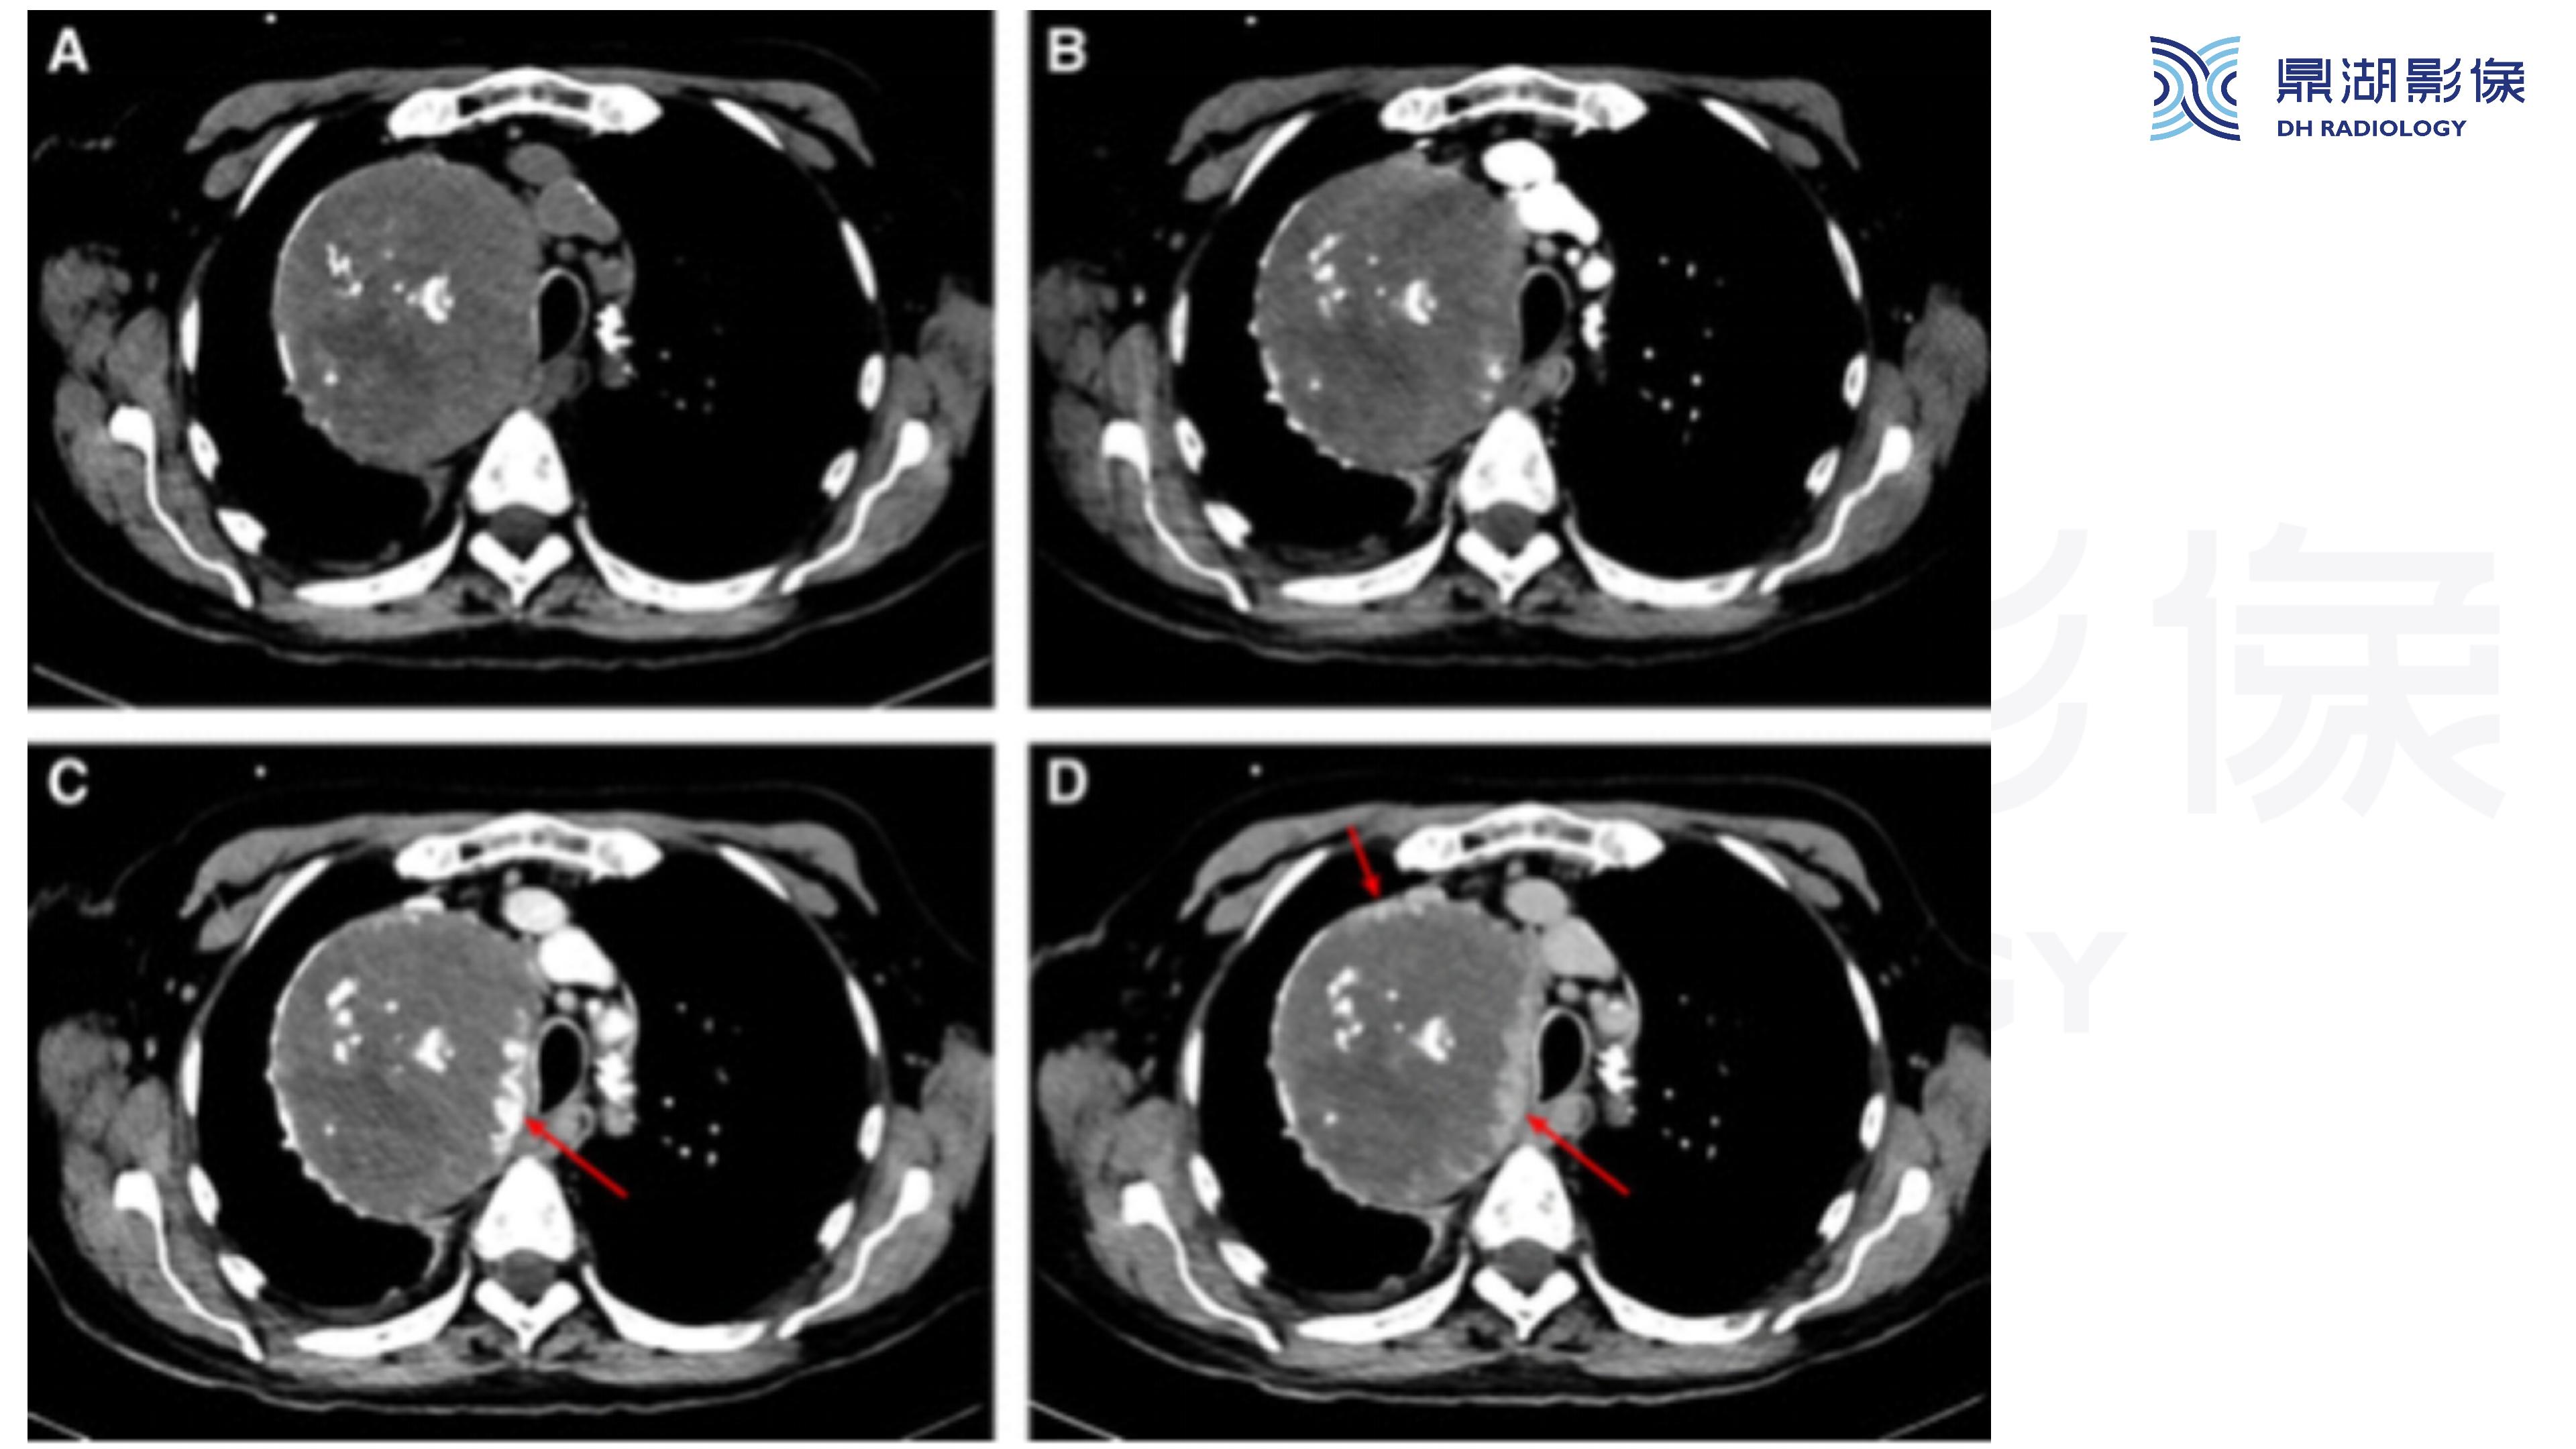

纵隔血管瘤-鼎湖社群读片病例